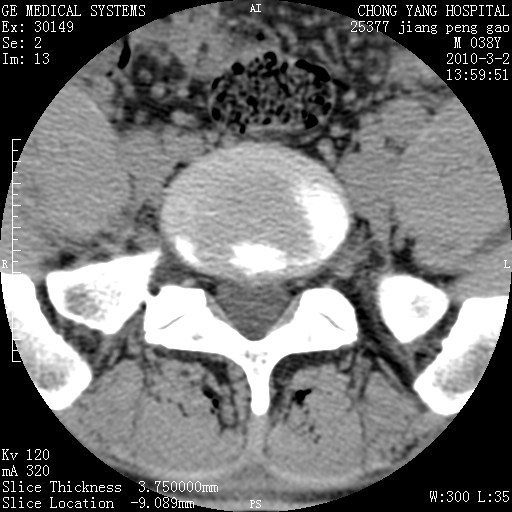

标题: CT24887:M38Y 反复腰痛 无外伤史 未做针灸 竖脊肌为何积气 [打印本页]

标题: CT24887:M38Y 反复腰痛 无外伤史 未做针灸 竖脊肌为何积气

软组织积气,考虑感染性病变。

退变,轻度增生/间盘膨出、l5椎后缘软骨结节。

肌间隙积气过多也为退变表现。